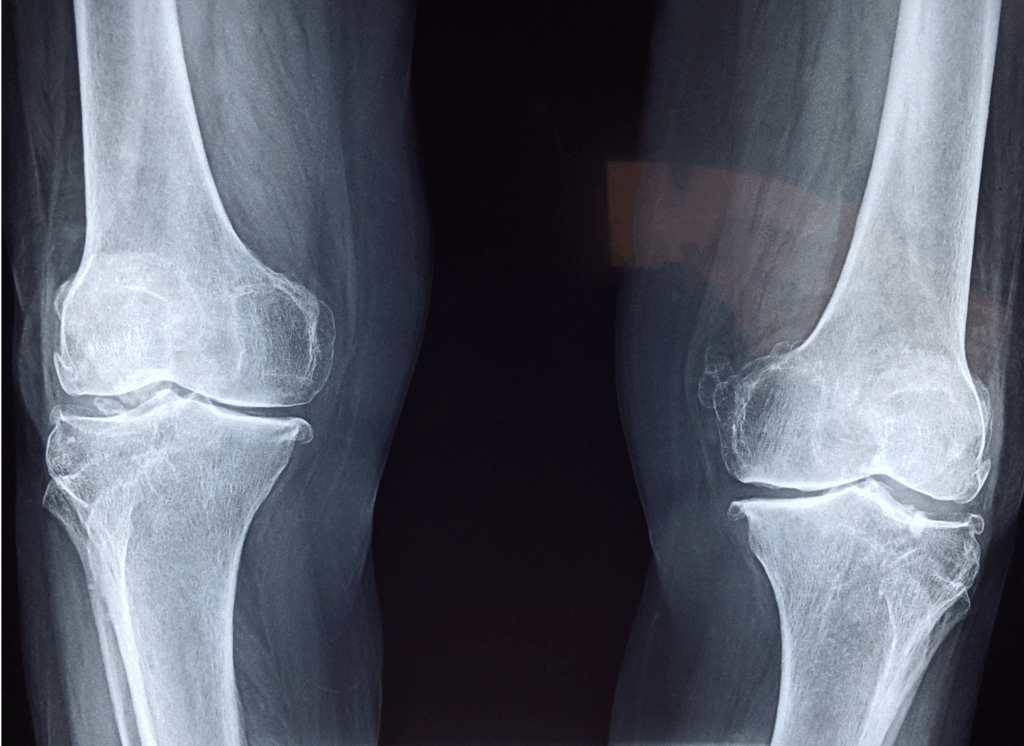

● 変形性膝関節症の一時的な炎症

「まだ変形性膝関節症と診断されたことはない」という方でも、

実は初期段階では立ち上がりの一瞬だけ痛むという症状が出ることがあります。

寒さや血流低下をきっかけに、関節内で炎症が起こると、ぎっくり膝のような痛みとして現れます。